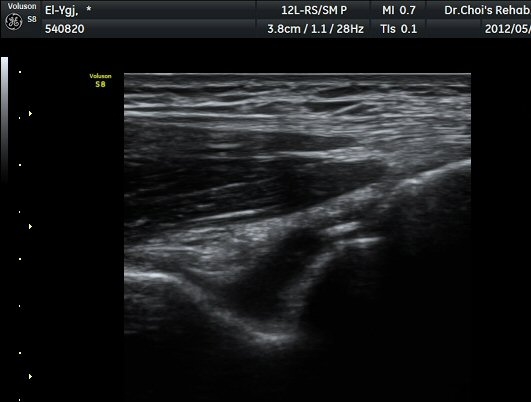

ÁֵοÍ(olecranon fossa) Á¾´Ü¸é°Ë»ç¿Í Ⱦ´Ü¸é°Ë»ç¿¡¼­ ÁÖµÎ¿Í ¼ö¾×Àú·ù¿Í °ø¿¡ÄÚ »À µ¢¾î¸®°¡

°üÂûµÈ´Ù(±×¸² 4, 5, 6).